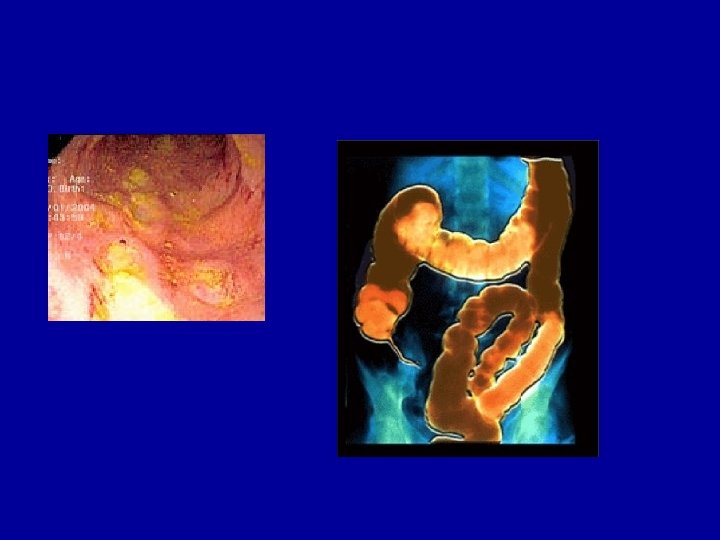

ETIOLOGIA E PATOGÊNESE • Lesões descontínuas (boca ao ânus) • Inflamação do cólon c preservação do reto • Lesão inicial – úlcera aftosa sobre placas de Peyer no int. delgado e agregados linfóides no cólon • Avanço – aumento úlceras, estreladas ou serpiginosas – coalescem, longitudinais ou transversais • Ilhas de mucosa n-ulcerada – desenho de ladrilhos • Fissuras desde a base das úlceras até serosa • Agregados linfóides na submucosa e externamente à muscular da túnica própria • Granulomas são comuns

ETIOLOGIA E PATOGÊNESE • Avaliação patológica pode não se correlacionar com as avaliações clínica e endoscópica • Parede intestinal espessada e rígida • Mesentério espessado, edematoso e contraído, fixa o intestino • Inflamação transmural – alças aderidas • Espessamento de tds camadas – estenose do lúmen

DIAGNÓSTICO • Exame endoscópico - enteroscopia - colonoscopia - cápsula endoscópica

DIAGNÓSTICO • Exame anatomopatológico aspectos macroscópicos: envolvimento total da parede, hiperemia e depósito de exudato no peritônio visceral - aspectos histológicos: alterações epiteliais, infiltrado de neutrófilos e monócitos no epitélio intestinal, abscessos - alterações totais na parede do intestino - acúmulo de gordura no mesentério